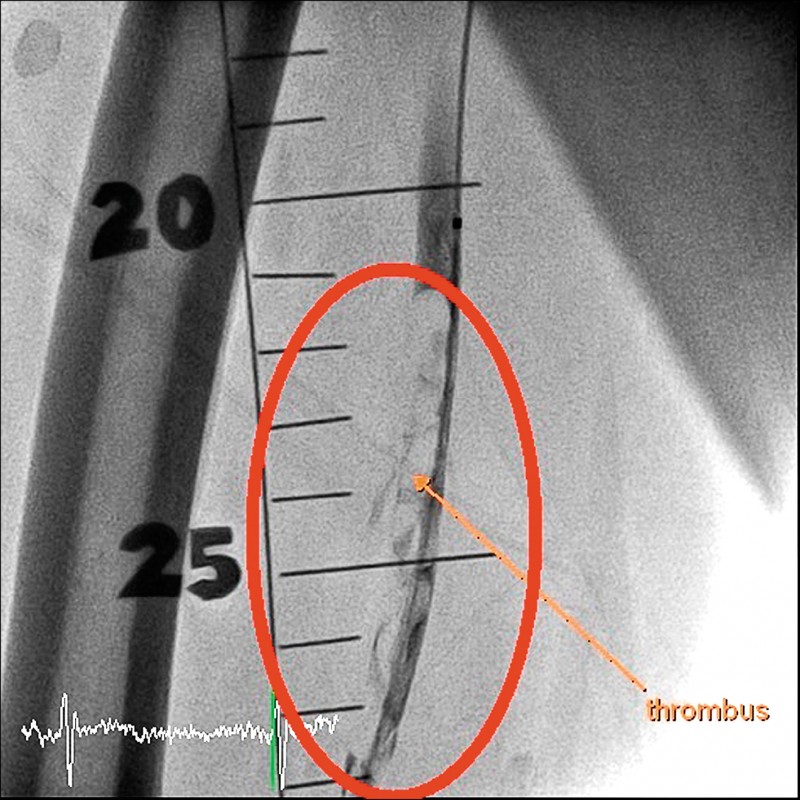

苗栗縣71歲陳姓老翁,從年輕時,就有抽菸習慣,是老菸槍,1週前突然覺得右腳冰冷、麻木,且小腿越來越痛,就醫檢查發現,他的右腳動脈被血栓塞住,導致大腿以下完全沒有血流。所幸,經醫師以「微創噴射機械除栓」手術,搭配導管溶栓治療,成功移除血栓、打通血管,保住他的右腳,免於被截肢的命運。

楊智鈞表示,過去傳統治療方式為使用藥物及開刀清除血塊,但出血風險很高,現行新技術「噴射機械除栓」設備,可以用微創的方式伸管子到血管裡把血塊清乾淨,再搭配藥物輔助,較傳統治療安全、成功率也較高。